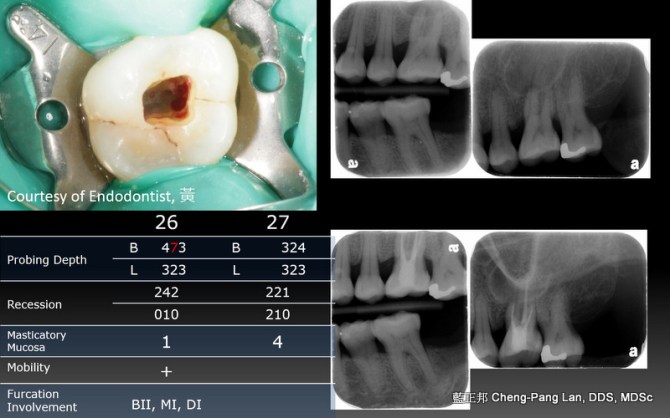

Root Amputation – Case A